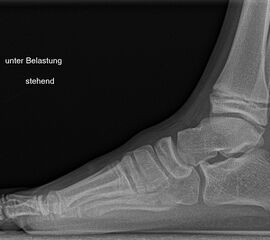

Knick-Senk-Platt-Fuß Korrektur mit dem Canalis Tarsi Spacer

In der Korrektur des schmerzhaften, aber flexiblen Knick-Senk-Fußes oder Plattfußes ist die Schraubenarthrorise mit einem Sinus tarsi oder besser bezeichnet als Canalis tarsi Spacer und alternativ mit einer Calcaneus-Stopp-Schraube seit vielen Jahren ein etabliertes Verfahren und führt zu einer kompletten Korrektur von flexiblen Knick- und Plattfuß-Fehlstellungen (Abb. 7). Die nötige Schnittlänge über dem Sinus tarsi beträgt für beide Verfahren 1 cm.

Abb. 7 a-e: Knick-Senk-Fuß prä- und postoperative Situation (a-b), ventrale und dorsale Ansicht (c-d). Laterale Ansicht des Hautschnittes über dem Sinus tarsi (e).